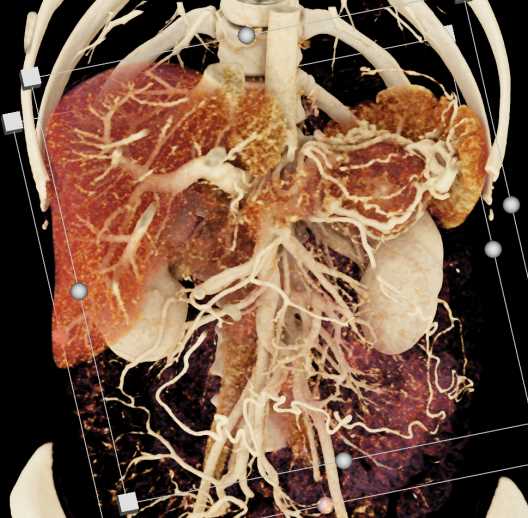

Neuroendocrine Tumor Pancreas